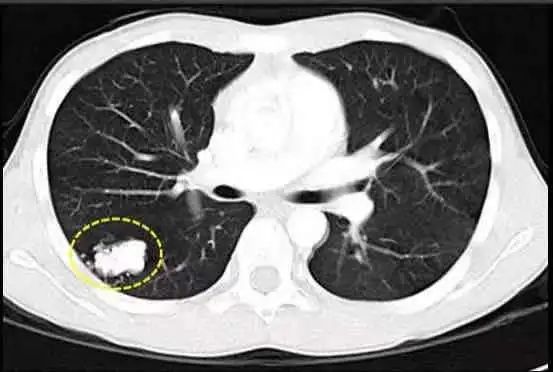

我国一项研究用多层螺旋CT对40岁以上健康人群进行筛查发现,有肺内孤立小结节(小于1厘米)的人占3.13%,在这些人中,肺结节是恶性(即肺癌)的概率是5%。

肺结节就是肺癌?

只有不到10%可能转变成肺癌,但是因为正处于结节状态、发展缓慢,以目前的医疗水平下是可以治好的!

退一步讲,就算肺结节真的查出是肺癌,绝大多数也是早期肺癌,只要正确处理,几乎不会影响病人的正常寿命。

所以,发现结节以后真的不可怕!